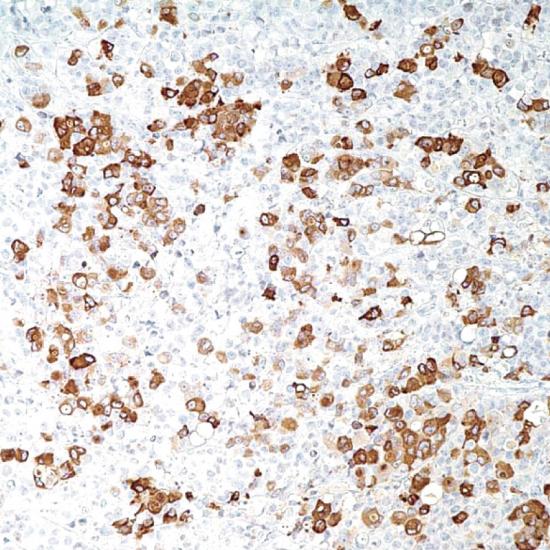

乳腺球蛋白是一個(gè)乳腺相關(guān)糖蛋白,它是一個(gè)分泌素家族(包括子宮球蛋白和lipophilin)成員的遠(yuǎn)親。與其他分泌素成員不同,乳腺球蛋白mRNA在乳腺組織中特異表達(dá)。在石蠟組織切片的檢測(cè)中,該抗體檢測(cè)乳腺癌組織中的乳腺球蛋白敏感度高達(dá)80%,如與其他乳腺特異標(biāo)記GCDFP-15聯(lián)合應(yīng)用時(shí),檢測(cè)乳腺癌組織中的乳腺球蛋白敏感度高達(dá)84%。檢測(cè)乳腺球蛋白,在鑒定原發(fā)癌是否發(fā)生轉(zhuǎn)移中起到至關(guān)重要的作用。